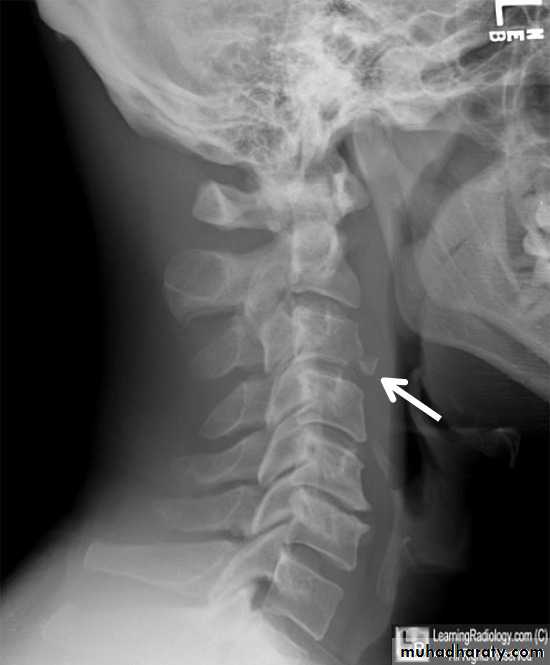

extension subluxation

frcature spine and peripheral nerve

A hyperextension

force may fracture the neural arch, especially of the atlas

Or fracture the dens (odontoid process) of the axis.

hyperextension may rupture the anterior longitudinal ligament and the

anulus fibrosus, forcing the vertebral bodies apart anteriorly (extension

subluxation) .

DIAGNOSISX RAY

Anterio posterior X ray radiograph.lateral radiographs with the head in flexion and extension may revealinstability that is not shown in the routine lateral film.

Treatment

It is unnecessary to attempt reduction, and all that is required is to support the

neck for 2 months to relieve pain. This may be achieved by a rigid plastic Collar.

In addition to N S A I

SOFT-TISSUE STRAIN OF THE CERVICAL SPINE

Mechanism of injury and pathology

At the moment of impact, the head is first

suddenly jolted forwards followed by rebound flexion of the spine.

And a second by extension of the neck.